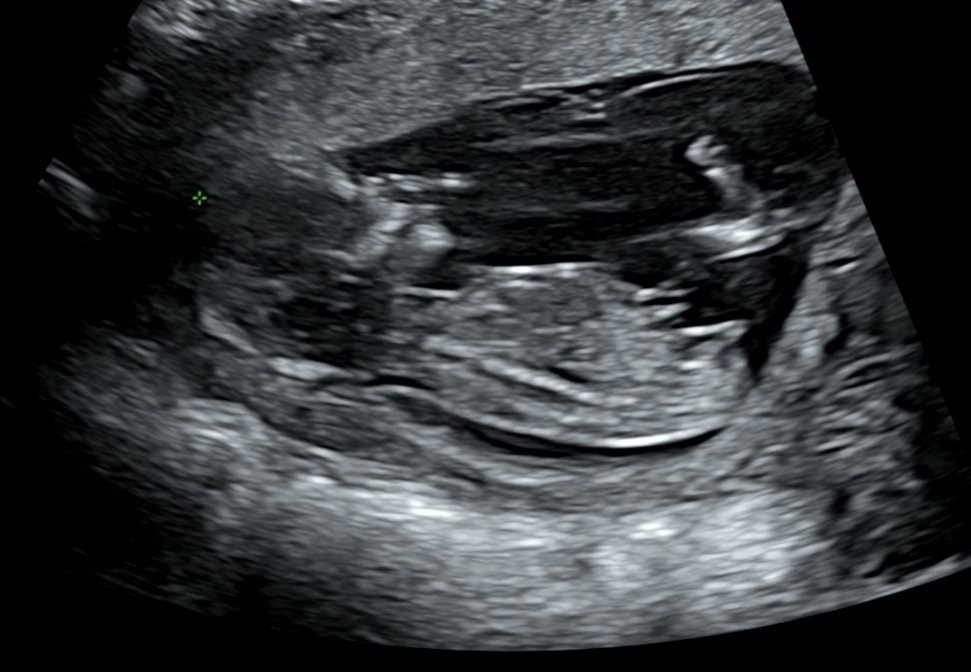

각도법 봐주세요!

저는 딸아이 같은데, 의사선생님이 왕자님같다고 하셔서요.. 각도법 고수님들 알려주세요 :)